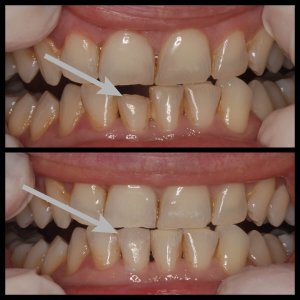

ΛΕΥΚΑΝΣΗ ΔΟΝΤΙΩΝ